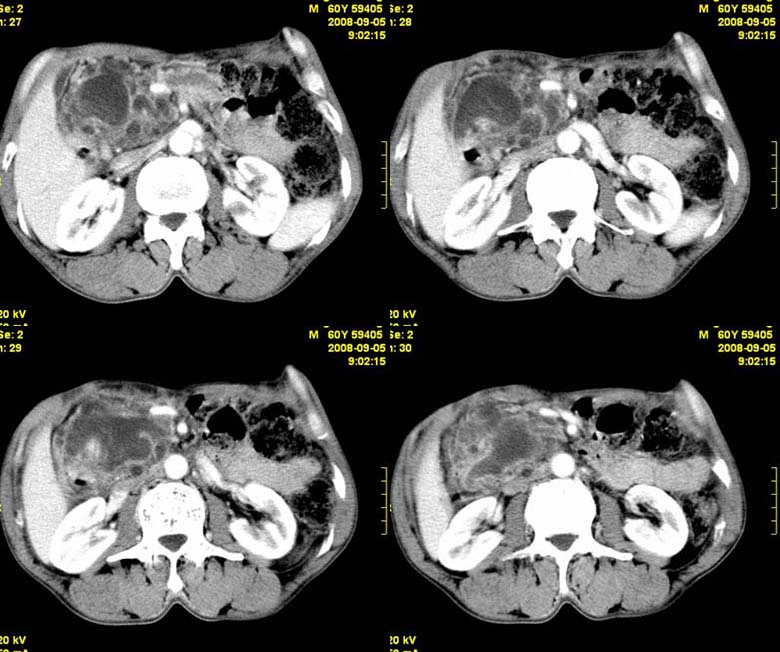

标题: CT15580:M60Y,胰腺病变,平扫+增强 [打印本页]

标题: CT15580:M60Y,胰腺病变,平扫+增强

患者,男, 60,既往有间歇腹痛病史多年,现右上腹痛,加重一月,伴右后背部疼痛,无黄疸,无发热。

胰头区增大,胰管明显扩张,不均匀强化,且与 周围结构不清,后背疼痛,考虑为胰腺头部胰腺癌。

胰头囊腺癌。

胰腺囊腺瘤可能性大,囊腺癌不除外.

同意胰头部囊腺癌。

胰头囊腺癌可能性大。

胰头囊腺癌

结合病史考虑慢性胰腺炎伴脓肿形成。

胰腺囊腺癌/慢性胰腺炎,建议查肿瘤标志物。